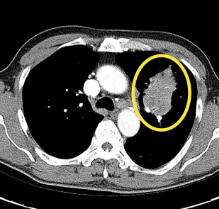

폐암 치료방법

초기라면 수술로도 충분히 치료가 가능하지만 말기이거나 전이가 된 상태라면 항암치료를 받게 됩니다. 최근에는 표적항암제라는 새로운 치료제도 개발되어 생존기간 연장 및 삶의 질 향상에 도움을 주고 있지만 부작용 우려가 있고 내성이 생길 수도 있어서 신중하게 선택해야 한다고 해요.